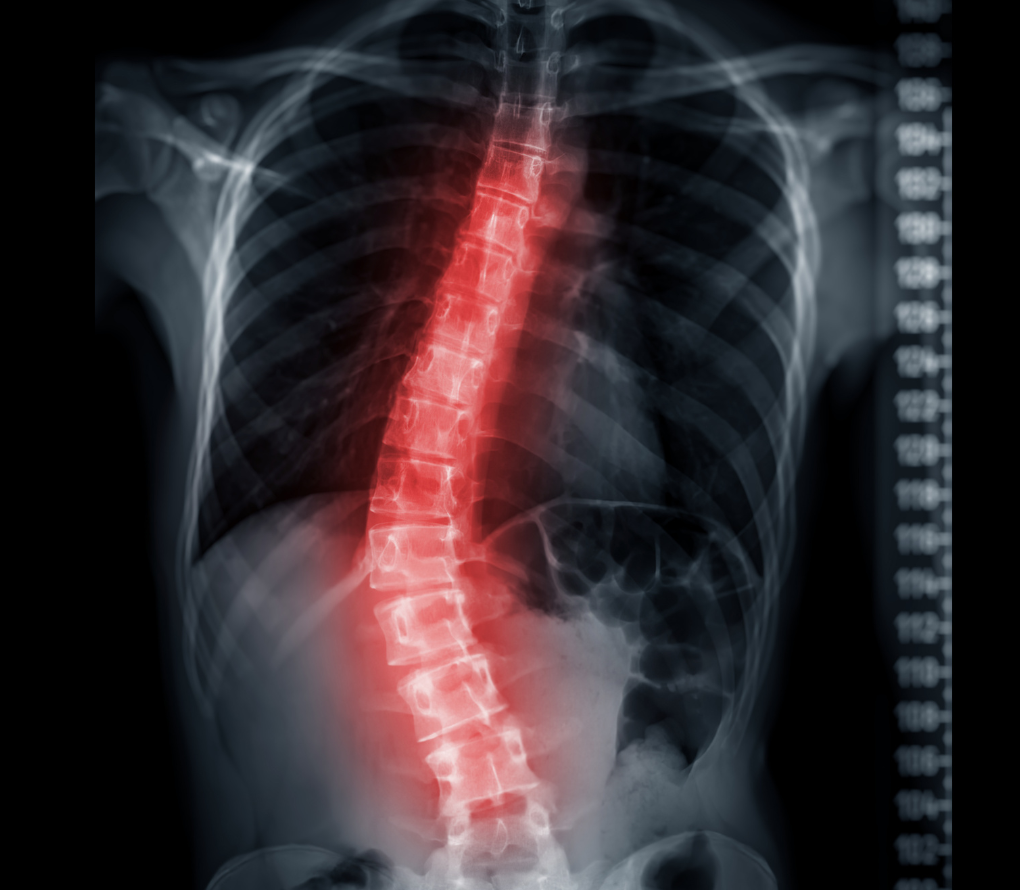

These surgeries correct abnormal curves of the spine using rods, screws, and fusion. They improve posture, breathing, and pain. Modern correction techniques achieve >70% curve correction with high patient satisfaction.